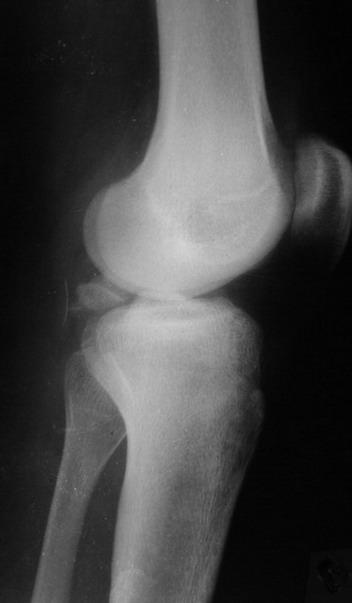

На основании небольшого личного опыта (4 пациента с отрывным переломом

задне-верхнего   края   большеберцовой   кости)  и  даннах  литературы

оптимальным считаю задний доступ, упомянутый David P. Zamorano.

В  3  из  4  случаев  мы  применили  винт,  проведенный ретроградно по

аналогии с фиксацией заднего края большеберцовой кости при переломах в

области  голеностопного  сустава.  В прищепке рентгенограммы одного из

наших  пациетов  до  операции и спустя полгода. Остальные 3 наблюдения